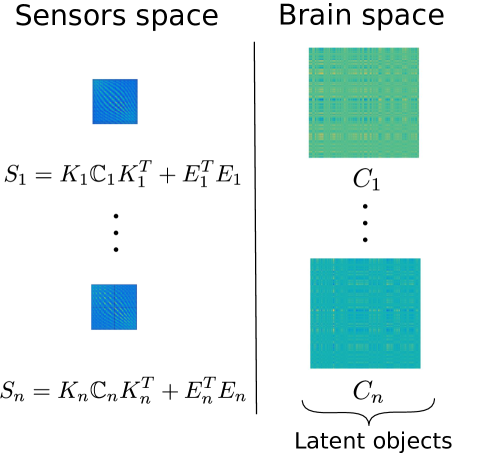

We consider the problem of estimating the PC functions in (5), and associated scores , from the observations . In Figure 3 we give an illustration of the introduced setting. Note that it would not be necessary to define the evaluation operator if the forward operators were defined to be functionals , relating directly the functional objects on the brain space to the real vectors on the sensors space. It is however the case that the operators are computed in a matrix form by third party software (see Section 6 for details) for a pre-specified set of points and it is thus convenient to take this into account in the model through the introduction of an evaluation operator .

We define a model for the PC covariance functions of from the set of indirectly observed covariance matrices, computed from the signals on the sensors space, and thus given by with

where , and are the sampling points associated with the operator . The forward operators act on both sides of the covariance functions , due to the linear transformation applied to the signals on the brain space before being detected on the sensors space. The term is an error term, where is a matrix such that each entry is an independent sample of a Gaussian distribution with mean zero and standard deviation . Model (6) could be regarded as an implementation of the idealized Problem 2, where the covariance operators are represented by the associated covariance functions. An illustration of the setting introduced can be found in Figure 4.

Consider now sample covariance matrices , each of size , representing different connectivity maps on the sensors space. Three of such covariance matrices, associated with three different individuals, are shown in Figure 2. Recall moreover that we denote with the brain surface template and with the set of subject-specific forward operators, relating the signal at the pre-specified points on the cortical surface with the signal detected on the sensors.